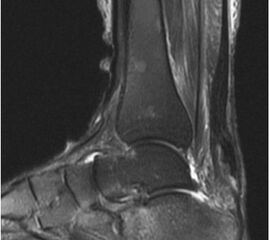

Abbildung 5

Der geübte Untersucher kann anhand des seitlichen Röntgenbildes die Diagnose einer Achillessehnenruptur stellen. Die Konturen des Kager-Dreiecks – gebildet von der ventralen Begrenzung der Achillessehne, der posterioren Tibiakante und der kranialen Kalkaneuskortikalis – verstreichen im Rupturfall (Kager 1939). Die MRT- Diagnostik spielt für die Primärdiagnostik der frischen Achillessehnenruptur eine untergeordnete Rolle und ist im Normalfall nicht notwendig. Anders verhält es sich bei den chronischen Rupturen. Hier ist die MRT ein wichtiges Diagnostikum insbesondere in Hinblick auf die Beurteilung der Sehnen- und Muskeldegeneration (Abb. 6).

Abbildung 6

Neben der strukturellen Wiederherstellung der Sehne ist die funktionelle Beurteilung des Muskels von entscheidender Bedeutung. Ist es bereits zu einer Degeneration der Muskeln gekommen, kann ein gutes funktionelles Ergebnis, trotz subtiler Sehnenrekonstruktion, nicht erreicht werden. Die Arbeitsgruppe um Hoffmann et al. 13 konnte in ihrer Arbeit zeigen, das es - ähnlich wie bei Patienten mit chronischen Supraspinatusrupturen - zu fettigen Degenerationen und Ödemen der Muskulatur kommt, die im MRT nachweisbar sind. Wir empfehlen die MRT- Untersuchung des gesamten Unterschenkels und nicht nur die rupturnahen Bereiche. Des Weiteren lässt die MRT eine Beurteilung der Degeneration der umliegenden Sehnenanteile zu. Die Computertomographie sollte nur in Ausnahmefällen zum Ausschluss von Begleitverletzungen (Abb. 7) durchgeführt werden und gibt uns sonst keinen weiteren Informationsgewinn.